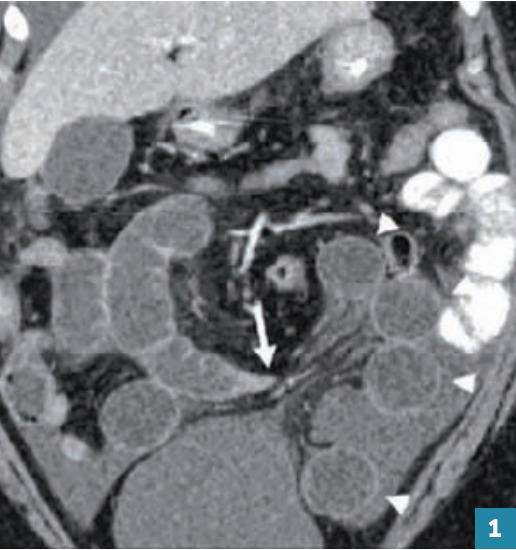

Le scanner abdomino-pelvien injecté, aisément accessible, est systématique lorsque la fonction rénale est suffisante. Il montre la dilatation du tube digestif en amont de la bride et permet dans certains cas un diagnostic topographique par la visualisation d’une jonction entre les segments dilatés et plats (fig. 1 ).

Le scanner abdomino-pelvien injecté, aisément accessible, est systématique lorsque la fonction rénale est suffisante. Il montre la dilatation du tube digestif en amont de la bride et permet dans certains cas un diagnostic topographique par la visualisation d’une jonction entre les segments dilatés et plats (